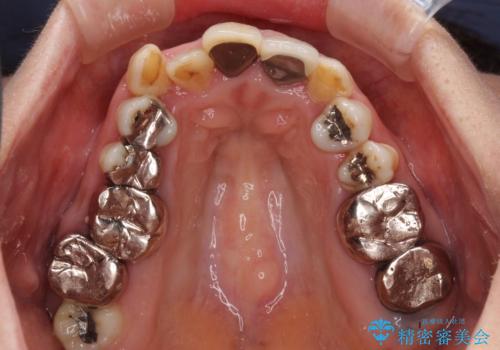

- 全顎的な歯列不正と、銀歯だらけの奥歯を気にして来院された患者様です。

奥歯の銀歯は、セラミッククラウンを装着するには歯の高さが不十分であり、そのままでは矯正治療を行うことが困難であるため、歯冠長延長術を行うこととしました。